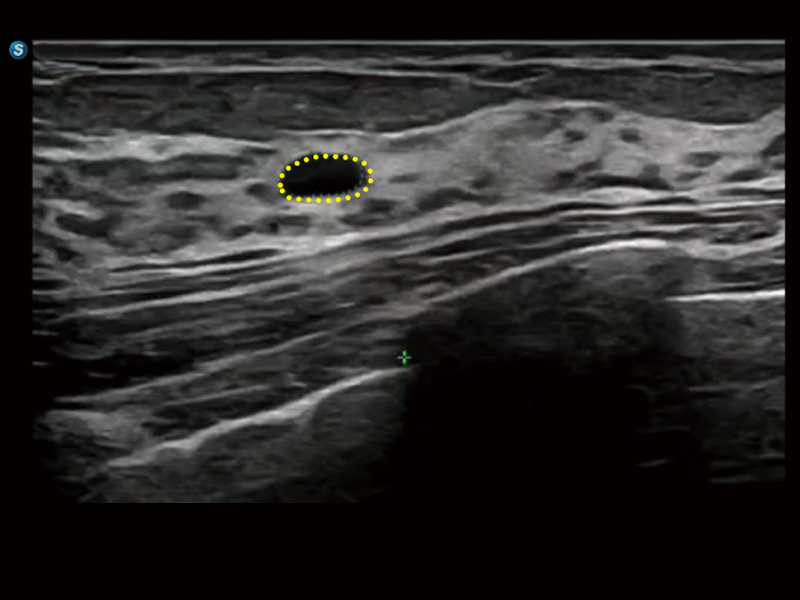

S80 提供多样化超声成像技术,可满足不同科室的需求,在助力扫查诊断和介入治疗中发挥着重要作用。

通过工作流协议、远程访问、自动探头激活和人体工程学优化设计等功能,旨在提高临床工作效率。